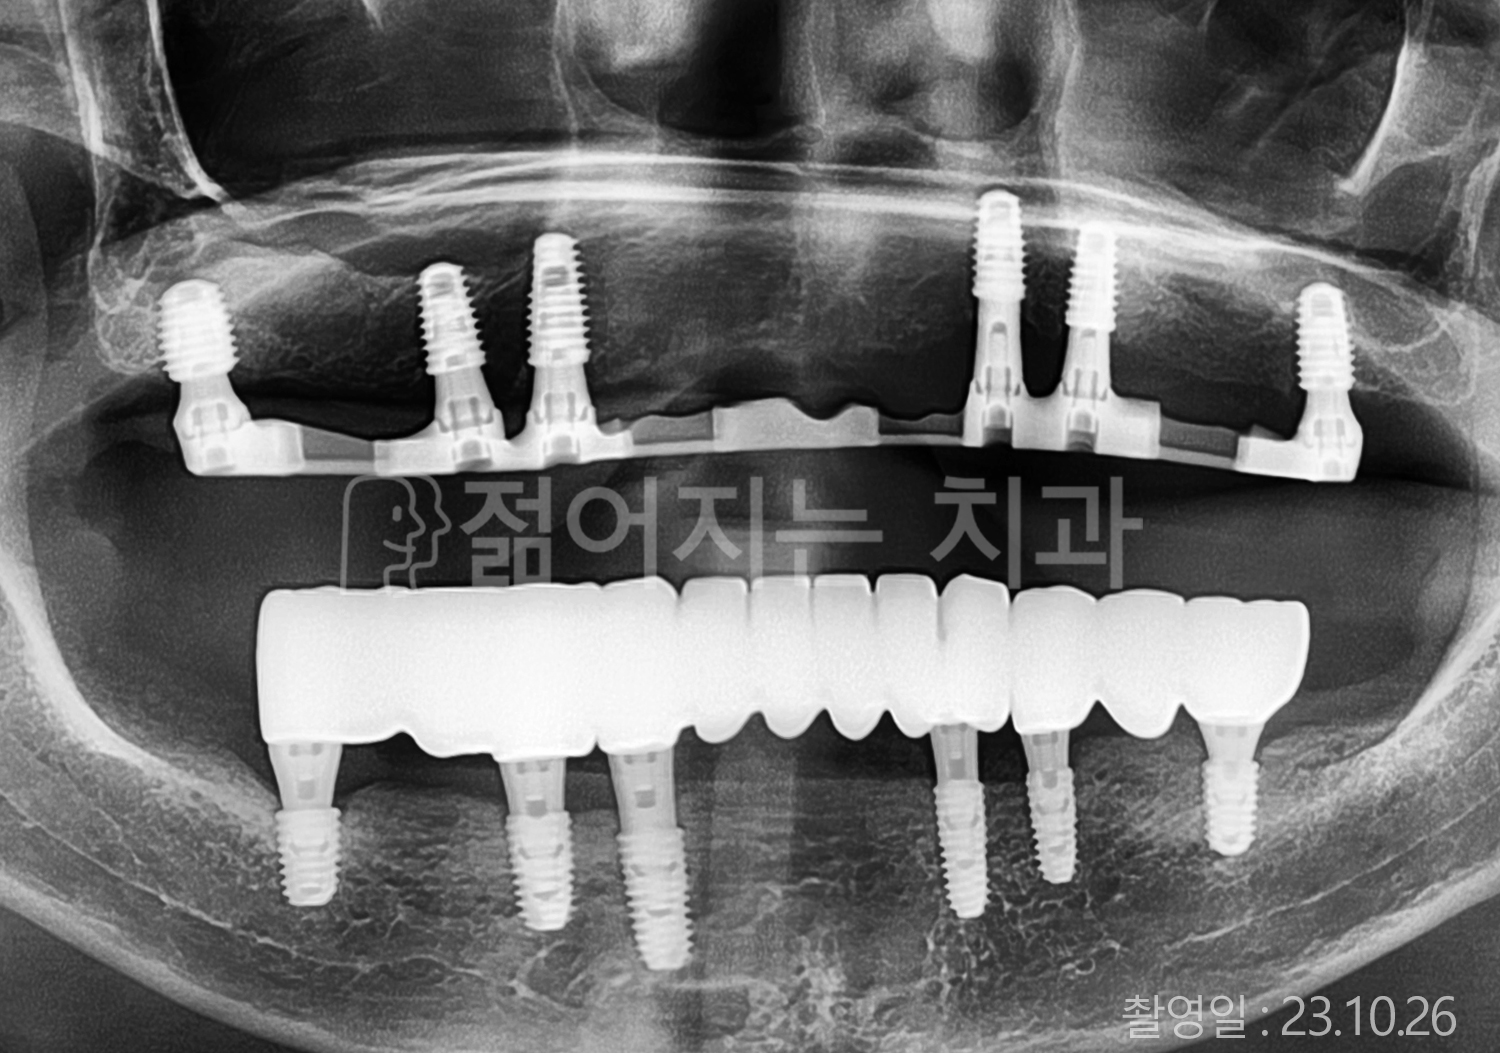

• 60대 고혈압, 고지혈증 전체치아 10개 이상 임플란트

• 70대 전체치아 10개 이상 임플란트

• 60대 전체치아 10개 이상 임플란트

• 50대 전체치아 10개 이상 임플란트

• 50대 고혈압, 고지혈증 전체치아 10개 이상 임플란트

• 60대 고혈압, 당뇨, 고지혈증 전체치아 10개 이상 임플란트

• 80대 고혈압, 당뇨, 골다공증 전체치아 10개 이상 임플란트

• 60대 고혈압 전체치아 10개 이상 임플란트

• 60대 고지혈증 전체치아 10개 이상 임플란트

• 60대 당뇨 전체치아 10개 이상 임플란트